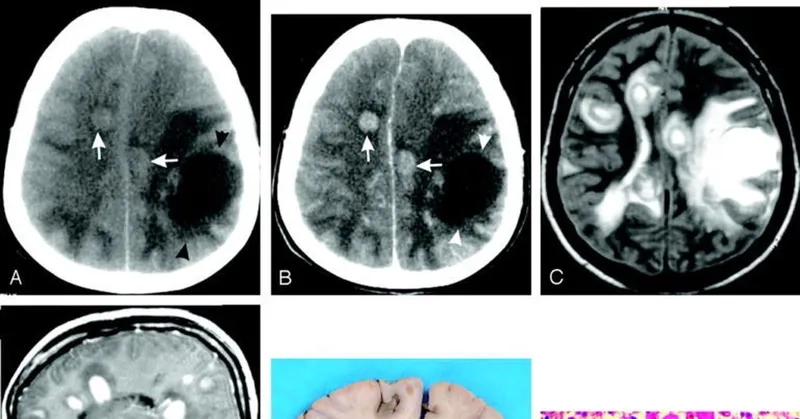

A medical chart of primary amebic meningoencephalitis (PAM)